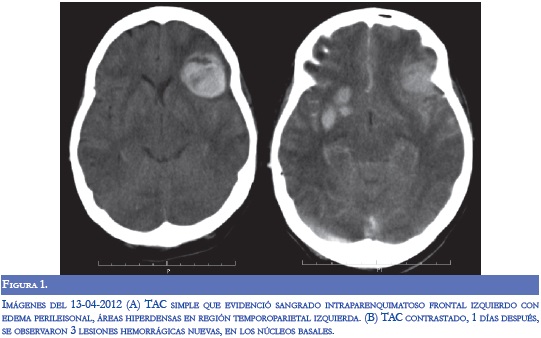

En la evaluación por neurología persistió disnéica con uso de musculatura intercostal, taquipnéica (FR: 32), taquicárdica (120) e inestabilidad hemodinámica (TA: 90/70), alerta con tendencia a la somnolencia, conteo vocal en 13, hipofonía, cuadriparesia 3/5 simétrica e hiporreflexia en 4 extremidades con respuesta plantar felxora bilateral. Se diagnosticó crisis miasténica, con inminencia de falla ventilatoria por lo cual se inició tratamiento con inmunolglobulina G humana y traslado a UCI. Durante la estancia hospitalaria, la paciente presentó respuesta inflamatoria sistémica, con aumento significativo de reactantes de fase aguda y enzimas hepáticas, secundario a bacteremia por Gram negativos, con requerimiento de soporte vasoactivo. Dos días después de finalizar manejo con inmunoglobulina, presentó focalización neurológica con mirada tónica hacia la izquierda, sin respuesta a estimulo externos, ni respuesta nociceptiva. Se realizó TC cerebral donde se evidenció sangrado en región frontal izquierda, otro en región cerebelosa derecha, ambos con edema perilesional, y disminución en la densidad en la sustancia blanca con aspecto de edema vasogénico (Figura 1). En la RM cerebral simple y contrastada se observaron lesiones hiperintensas subcorticales bilaterales con áreas de hemorragia (Figura 2). Se realizó panangiografia cerebral con vasoespasmo de la ACM izquierda M1 y ACA A1 derecha sin patrón de vasculitis. Durante su estancia hospitalaria presentó mejoría clínica y a las dos semanas se observó mejoría del edema vasogénico en las neuroimágenes (Figura 3).